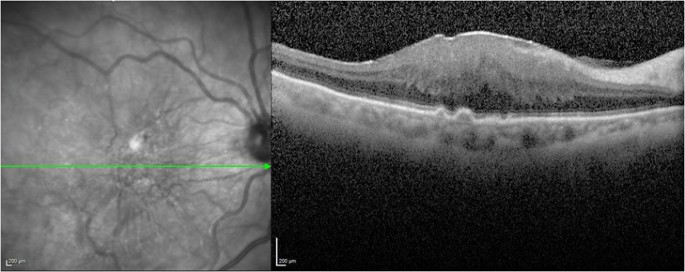

The extent of ERM-retinal adhesion was then categorized as focal, broad, or complete.23 Focal adhesion was defined as ERM-retinal adhesion <50%; broad adhesion between 50 and 90%; and complete adhesion >90% (Figures 1 and 2). In cases where the classification did not agree between the observers for any of the anatomic locations, the type of the ERM adherence to the retina was determined by a third masked observer.